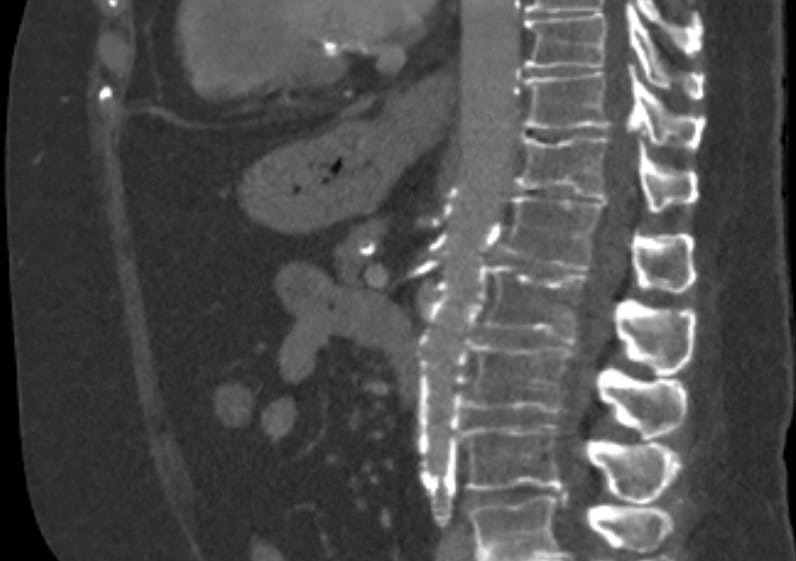

Mesenteric ischemia CT angiogram

Sagittal view of a CT angiogram demonstrating atherosclerosis at the ostium of the celiac artery and SMA